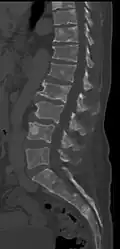

The diagnostic examination of a person with suspected multiple myeloma typically includes a skeletal survey. This is a series of X-rays of the skull, axial skeleton, and proximal long bones. Myeloma activity sometimes appears as "lytic lesions" (with local disappearance of normal bone due to resorption) or as "punched-out lesions" on the skull X-ray ("raindrop skull"). Lesions may also be sclerotic, which is seen as radiodense.[76] Overall, the radiodensity of myeloma is between −30 and 120 Hounsfield units (HU).[77] Magnetic resonance imaging is more sensitive than simple X-rays in the detection of lytic lesions. An MRI may supersede a skeletal survey, especially when vertebral disease is suspected. Occasionally, a CT scan is performed to measure the size of soft-tissue plasmacytomas. Nuclear Medicine Bone scans are typically not of any additional value in the workup of people with myeloma (no new bone formation; lytic lesions not well visualized on nuclear bone scan).

Pathological fracture of the lumbar spine due to multiple myeloma -